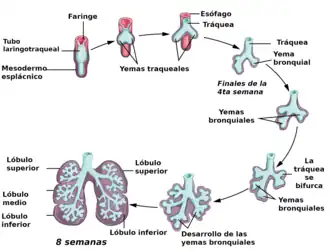

El pulmón de los vertebrados tiene su origen embriológico en un repliegue del esófago. Por lo cual está formado del endodermo, doblado secundariamente del mesodermo para la vascularización. Todos los cordados poseen en algún momento de su ciclo vital la «faringe perforada» (faringotremia o hendiduras branquiales)que surgió en los procordados como un mecanismo de alimentación por filtración. El sistema funciona al introducir agua con partículas alimenticias, las cuales quedan adheridas a la pared de la faringe por secreciones mucosas, mientras que el agua vuelve a salir por las hendiduras faríngeas. Al pasar los protovertebrados de un sistema de vida filtrador a otro depredador, la faringe se modificó como un aparato de alimentación muscular, a través del cual se podía bombear agua expandiendo y contrayendo la cavidad. En los peces se ha heredado esta faringe perforada pero ya no se utiliza para alimentarse y los tabiques faríngeos se sitúan en las branquias.